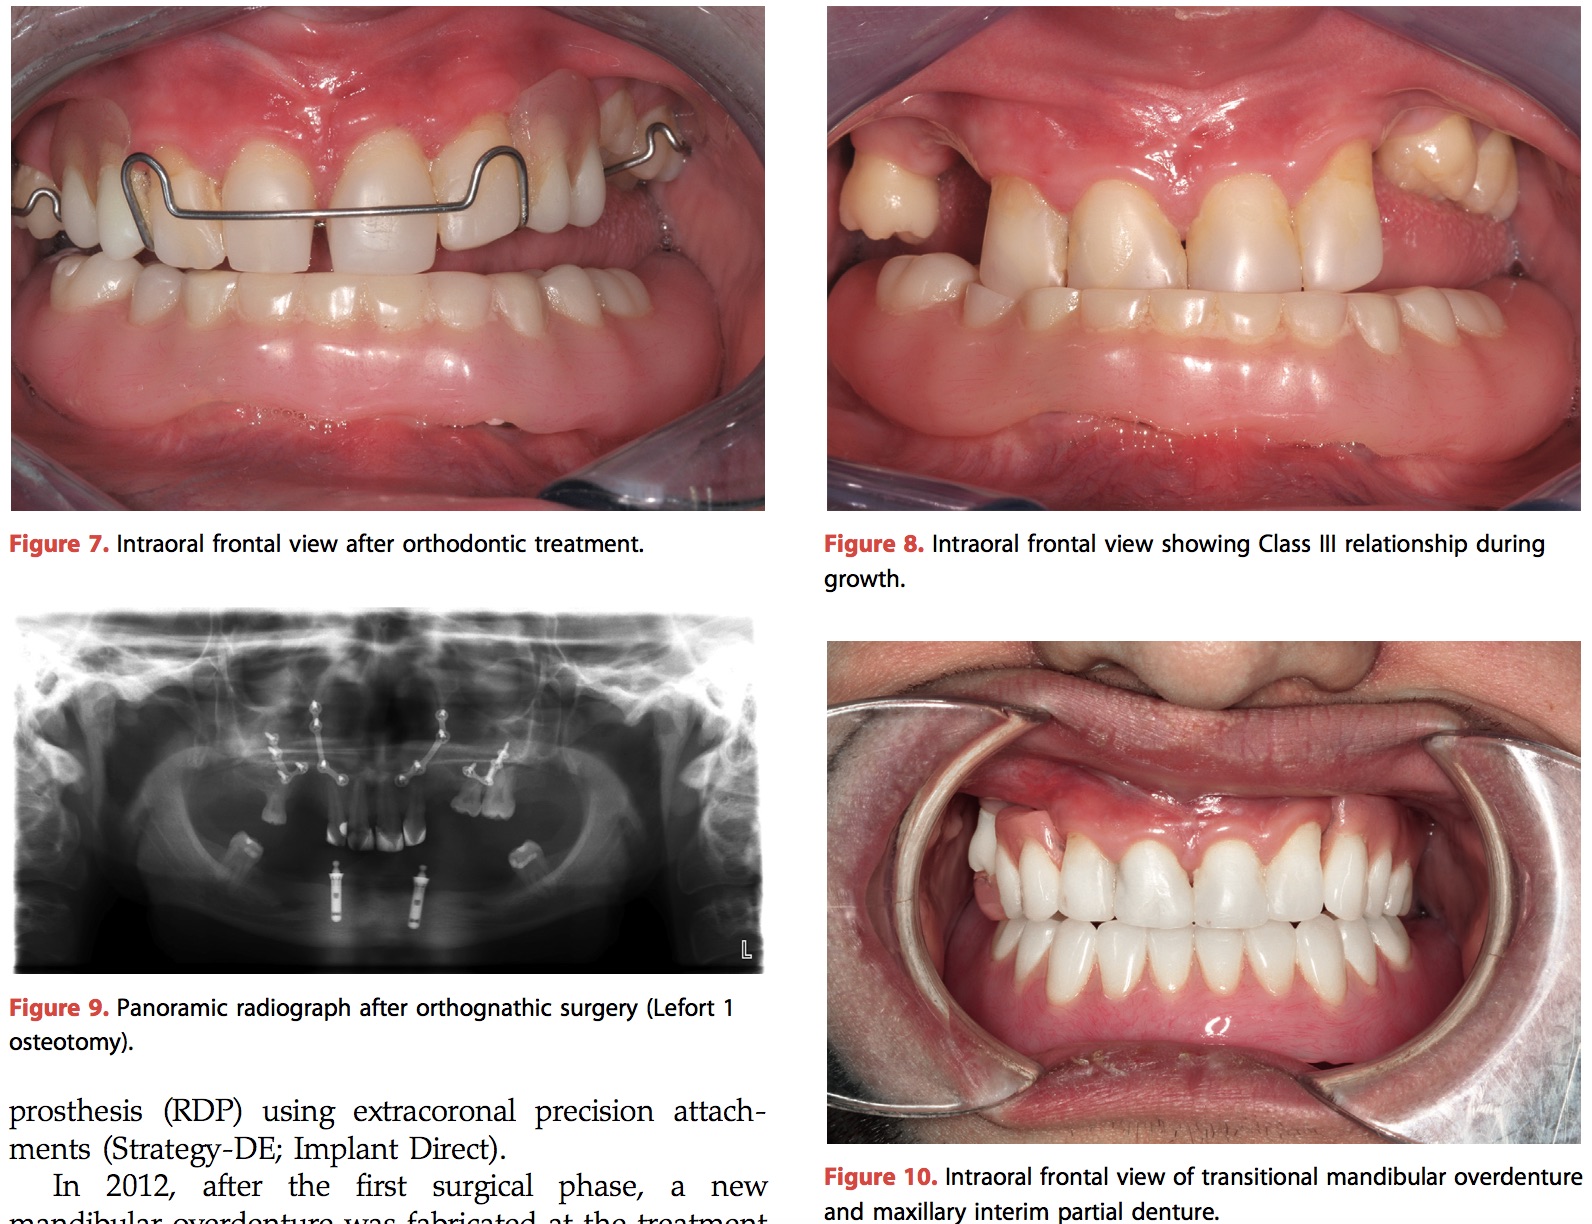

這篇文章可以說是在治療這類罕見疾病(外胚層發育不良,牙齒會有嚴重缺陷)很有參考價值的case report,尤其是他追蹤了13年。在早期的時候就決定在下顎做植牙,然後overdenture,等成年後再加種改成implant supported fixed denture,是很合理的。而上顎做了一些矯正,然後再用OGS改,再植牙做implant assisting RPD。很漂亮的case,相信這個患者是有得到牙科正面的協助的。